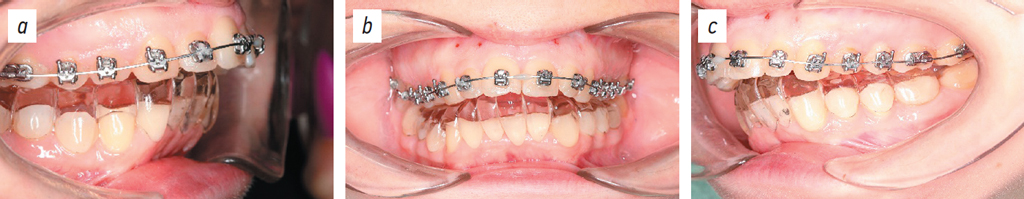

The outcomes of orthodontic treatment are presented in Figs. 19–21.

Fig. 19. Dental arches: lateral right projection (a), posteroanterior projection (b), lateral left projection (c).

Рис. 19. Зубные ряды: боковая правая проекция (a), передняя проекция (b), боковая левая проекция (c).

Fig. 20. Occlusal projection of the upper dental arch (a) and the lower dental arch (b).

Рис. 20. Окклюзионная проекция верхнего зубного ряда (a), нижнего зубного ряда (b).

Fig. 21. Photo of the patient’s face during the treatment: right three-quarter view with a smile (a), frontal view with a smile (b), left three-quarter view with a smile (c).

Рис. 21. Фотография лица пациенткина этапе лечения: 3/4 оборота с улыбкой справа (a), с улыбкой анфас (b), ¾ оборота с улыбкой слева (c).

This clinical case demonstrated a 2-fold reduction in treatment duration compared to conventional approaches.